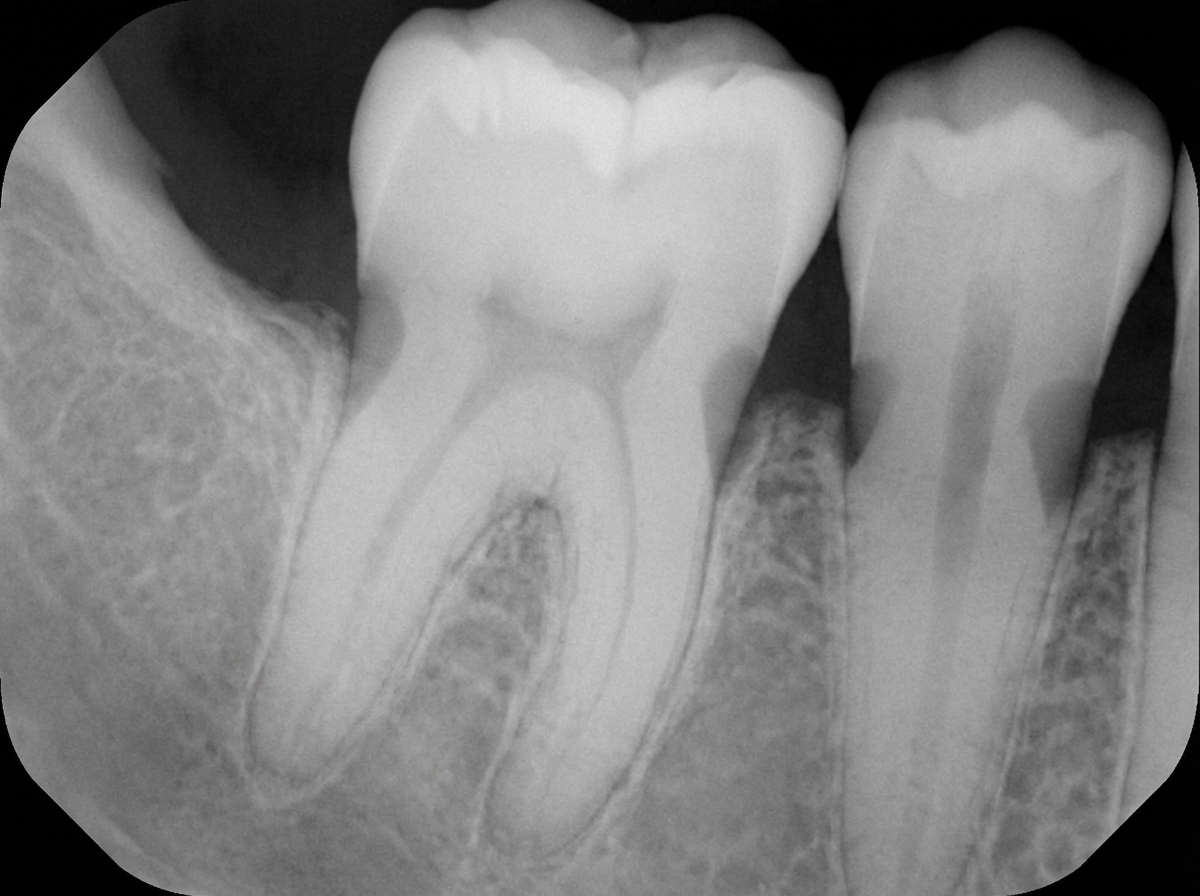

A 44-year-old male presents with a swelling on the palate. On intraoral examination, a marked swelling is seen in the region of the palatine papilla, situated mesial to the roots of teeth 11 & 21. These teeth respond normally to vitality tests. An IOPA radiograph is provided. What is the most probable diagnosis?

Explanation: ***Nasopalatine cyst*** - Located in the **midline anterior maxilla** between the central incisors (teeth 11 & 21), arising from **epithelial remnants** of the **nasopalatine duct**. - Characteristically presents with **vital teeth** and shows a **heart-shaped radiolucency** on IOPA due to **nasal spine superimposition**. *Globulomaxillary cyst* - Typically located between the **lateral incisor and canine**, not in the midline between central incisors. - Would present as a **pear-shaped radiolucency** causing **divergence of roots** between lateral incisor and canine. *Radicular cyst* - Associated with **non-vital teeth** showing **negative response** to vitality tests due to **pulpal necrosis**. - Arises from **periapical granuloma** following chronic **apical periodontitis**, which is inconsistent with vital teeth. *Cyst of palatine papilla* - Represents a **soft tissue cyst** of the **incisive papilla** without significant **bony involvement**. - Would not show characteristic **radiolucent changes** on IOPA radiograph as seen in this case.